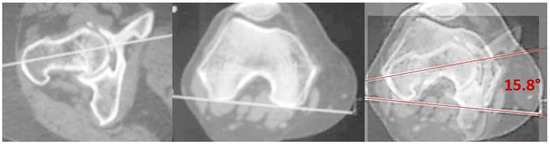

2.2. Measurements

| Femoral Version | 16.00° ± 4.53° (15.22°–16.78°) | 13.16° ± 4.37° (12.31°–14.01°) | 0.0001 |